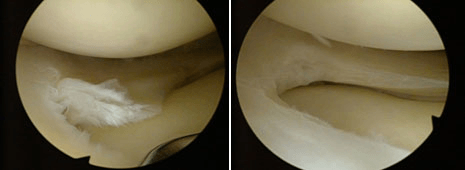

Chirurgia meniscului prin remodelare

Meniscectomia (remodelarea meniscului) este o intervenție chirurgicală artroscopică prin care se îndepărtează porțiunea ruptă de menisc (meniscectomie parțială) sau aproape întregul menisc (meniscectomie subtotală). Metoda artroscopică este minim invazivă, iar în cazul unui traumatism al ligamentului încrucișat, va include și repararea acestuia, pentru evitarea apariției gonartrozei (artroza progresivă a genunchiului).